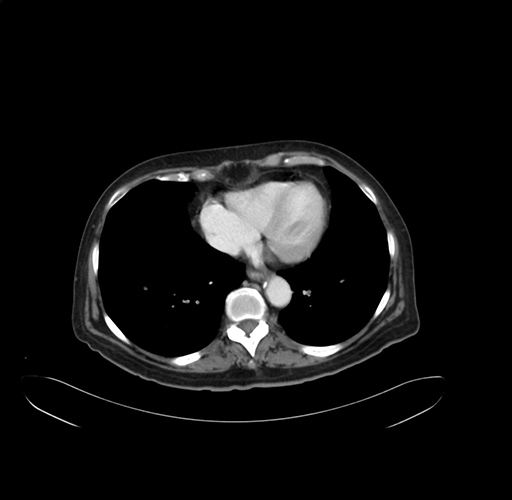

Pre-Chemo: Axial Venous